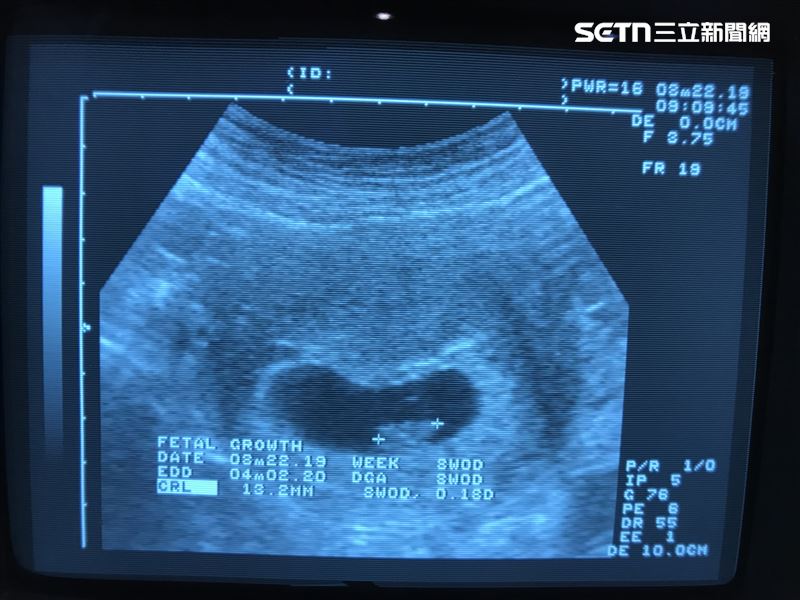

B女士接受《三立新聞網》電話訪問時說,從年輕努力到現在做了很多次試管,已經是卵巢早衰的情況幾乎找不到卵子了,借卵生子確實是讓夫妻倆燃起一絲希望,可以完成他們為人父母的心願,他說,在尋求跨國代孕之前諮詢過領養小孩,但包括過程、手續、等待時間、能否順利領養變數都很大,才選擇接受代孕建議。

A先生說,結婚時他跟太太都不到30歲,婚後積極備孕仍沒有下文,包括人工受孕、試管嬰兒等手術都做過,偶然發現有協會協助不孕夫妻到海外代孕燃起滿滿希望,因為相信協會以及吳姓理事長自己到烏克蘭接受代孕生下小孩的活招牌,走上跨境代孕的路。